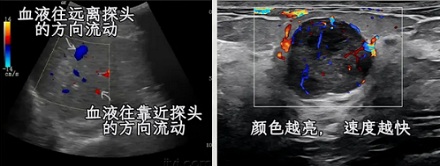

✔ C 超 /D 超 (彩超) (Color Doppler Flow lmaging/Doppler)

临床上其实就是彩超,不过有些医院会因为开头字母把它们叫成 C 超/D 超。

彩超指的是彩色多普勒血流成像。不仅能显示灰度图像,还可以显示血液流动速度和方向。